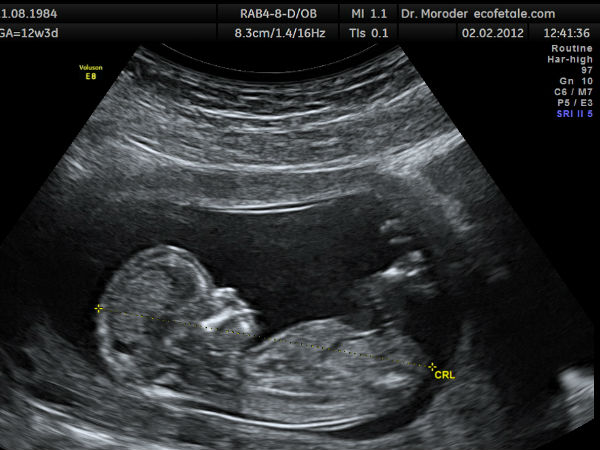

'அல்ட்ராசவுண்ட்' என்பதை தமிழில் மீயொலி என்கிறார்கள். மனித செவியால் 20 முதல் 20,000 ஒலி அலைகள் கொண்ட ஒலிகளைத்தான் கேட்க முடியும் என்பதால் மீயொலிதனை மனிதர்களால் கேட்க இயலாது. நாய்கள், டால்பின்கள், வௌவால்கள் போன்ற சில விலங்குகளால் மட்டுமே கேட்க முடியும். அப்படியான மீயொலியைக் கர்ப்பம் தரித்திருக்கும் தாய்மாரின் வயிற்றில் இருக்கும் குழந்தையின் நிலையை அறிந்துக் கொள்ளவும் பயன்படுத்தப்படுகிறது, அந்த மருத்துவ முறையை சோனோகிராஃபி (sonography) என்கிறார்கள்.

எட்டு முதல் பத்து வாரம் நிரம்பிய இந்த கருவின் வெளிப்புறத்தில் நிர்வாண உடலோடு ஒரு உருவம் நிற்பதை தெளிவாக காண முடிகிறது.